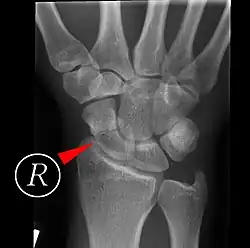

Fractures of the scaphoid are the most common of the carpal bone injuries, because of its connections with the two rows of carpal bones.[1]: 177

The scaphoid can be slow to heal because of the limited circulation to the bone. Fractures of the scaphoid must be recognized and treated quickly, as prompt treatment by immobilization or surgical fixation increases the likelihood of the bone healing in anatomic alignment, thus avoiding mal-union or non-union.[6] Delays may compromise healing. Failure of the fracture to heal ("non-union") will lead to post-traumatic osteoarthritis of the carpus.[1]: 189 One reason for this is because of the "tenuous" blood supply to the proximal segment.[3] Even rapidly immobilized fractures may require surgical treatment, including use of a headless compression screw such as the Herbert screw to bind the two halves together.

Healing of the fracture with a non-anatomic deformity (frequently, a volar flexed "humpback") can also lead to post-traumatic arthritis. Non-unions can result in loss of blood supply to the proximal pole, which can result in avascular necrosis of the proximal segment.

Scaphoid fractures may be difficult to diagnose via plain x-ray. A repeat x-ray may be required at a later date, as might cross-sectional imaging via MRI or CT scan.[6]